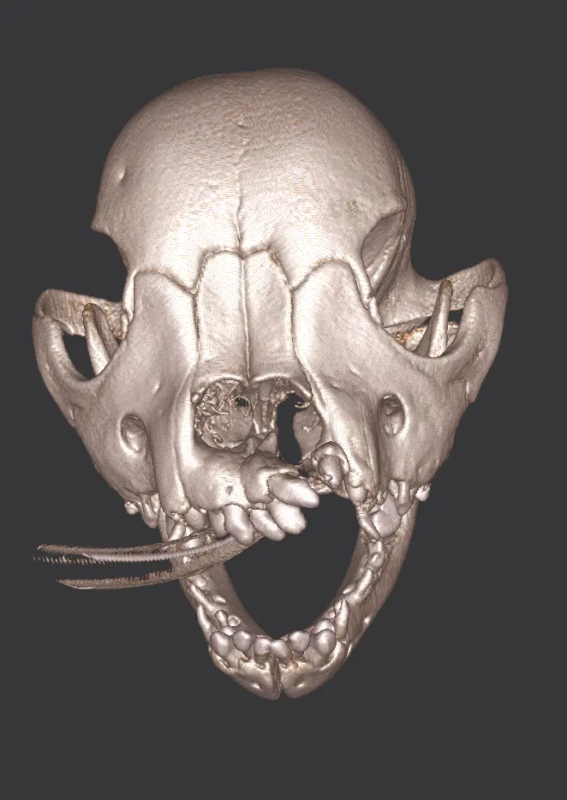

Repair of Maxillofacial Fracture

Pets can be involved in trauma that can cause fractures to their head, teeth, and jaw bones. Correctly repairing these fractures is extremely important for your pet to have normal function of their mouth. If a jaw fracture is allowed to heal in an abnormal position, your pet may have great difficulty chewing and can be in significant pain. Many fractures can be successfully treated with minimally invasive oral procedures, but more complicated cases may require bone plating techniques. The Center offers cone beam CT imaging which provides extremely detailed images of the bones of the head and skull. Advanced imaging with CBCT facilitates selection of the best surgical technique to get your pet back to eating and comfort as soon as possible.